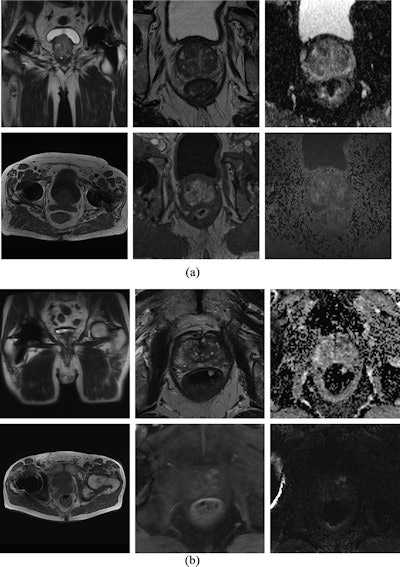

In this retrospective multicenter study, the investigators compared results from 70 patients with hip replacements who underwent 1.5-tesla mpMRI prostate cancer exams (Magnetom Avanto fit, Siemens Healthcare) and 70 patients who had 3-tesla exams (Magnetom TIM Trio, Prisma or Skyra; Siemens Healthcare). The diagnostic mpMRI studies were evaluated by three readers with three, six, and 11 years of experience.

The overall diagnostic value and prostate imaging quality score (PI-QUAL) were assessed. Artifact severity in the localizer and mpMRI sequences (T2W, diffusion-weighted imaging, and dynamic contrast-enhanced imaging, or DCE) was scored on a three-point scale. The researchers analyzed correlations between diagnostic value and artifacts. The primary endpoint was the diagnostic value of mpMRI-scans at 1.5 tesla and 3 tesla.

Artifacts that impaired image quality substantially occurred at both field strengths in about 30% of patients, the authors found. Artifacts in all MRI sequences and in the localizer at 3 tesla correlated significantly with the diagnostic value, whereas T2-weighted sequences at 1.5-tesla were not as strongly correlated as in 3-tesla examinations, the researchers found.

Boschheidgen and colleagues observed a PI-QUAL score of less than 3 in 19 scans at 3 tesla and in 22 scans at 1.5 tesla; 39% of the scans at 1.5 tesla and 30% of the scans at 3 tesla exhibited excellent image quality with a PI-QUAL score of 5.